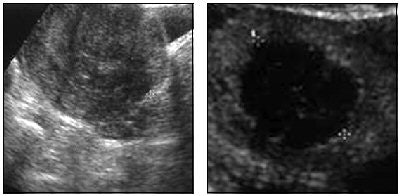

| A 42-year-old woman with menorrhagia and pelvic pain due to 4.6-cm uterine myoma. Left, suprapubic sonogram shows hypoechogenic intramural myoma. Right, contrast-enhanced sonogram after radiofrequency ablation shows anechogenic avascularized round area (treated myoma) surrounded by normal vascularized myometrium confirming success of ablation and absence of myometrial injury. Recaldini C, Carrafiello G, Lagana D, Cuffari S, Bergamini V, Ghezzi F, Fugazzola C, "Percutaneous Sonographically Guided Radiofrequency Ablation of Medium-Sized Fibroids: Feasibility Study" (AJR 2007; 189:1303-1306). |

The mean follow-up period was nine months and included transvaginal sonography as well as quality-of-life (QOL) questionnaires. According to the results, no repeat intervention was needed during the follow-up period. Based on the last follow-up visit, the median fibroid volume was reduced to 8.07 cm3 while the median diameter shrunk to 2.3 cm. The median QOL score 63.92.

The authors offered several take-home messages from this preliminary study. First, patients with myomas larger than 6 cm -- or multiple myomas -- are ineligible for this single-procedure technique. Also, the use of contrast-enhanced sonography offers precise targeting in highly vascularized areas, in addition to depicting changes in tissue echotexture during the procedure. Finally, interventional radiologists are best-suited to perform this procedure as accessing superficial as well as deep organs is highly operator-dependent.